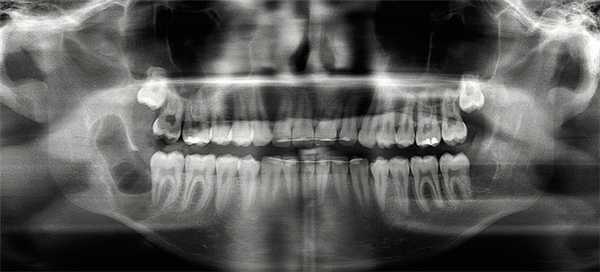

После операции была снова сделана рентгенгограмма (рис. 2) .

Рис. 2. Послеоперационная контрольная рентгенограмма: состояние после оперативного удаления 48 зуба мудрости, энуклеации тканей кисты в области 48 зуба и кюретажа образовавшейся костной полости